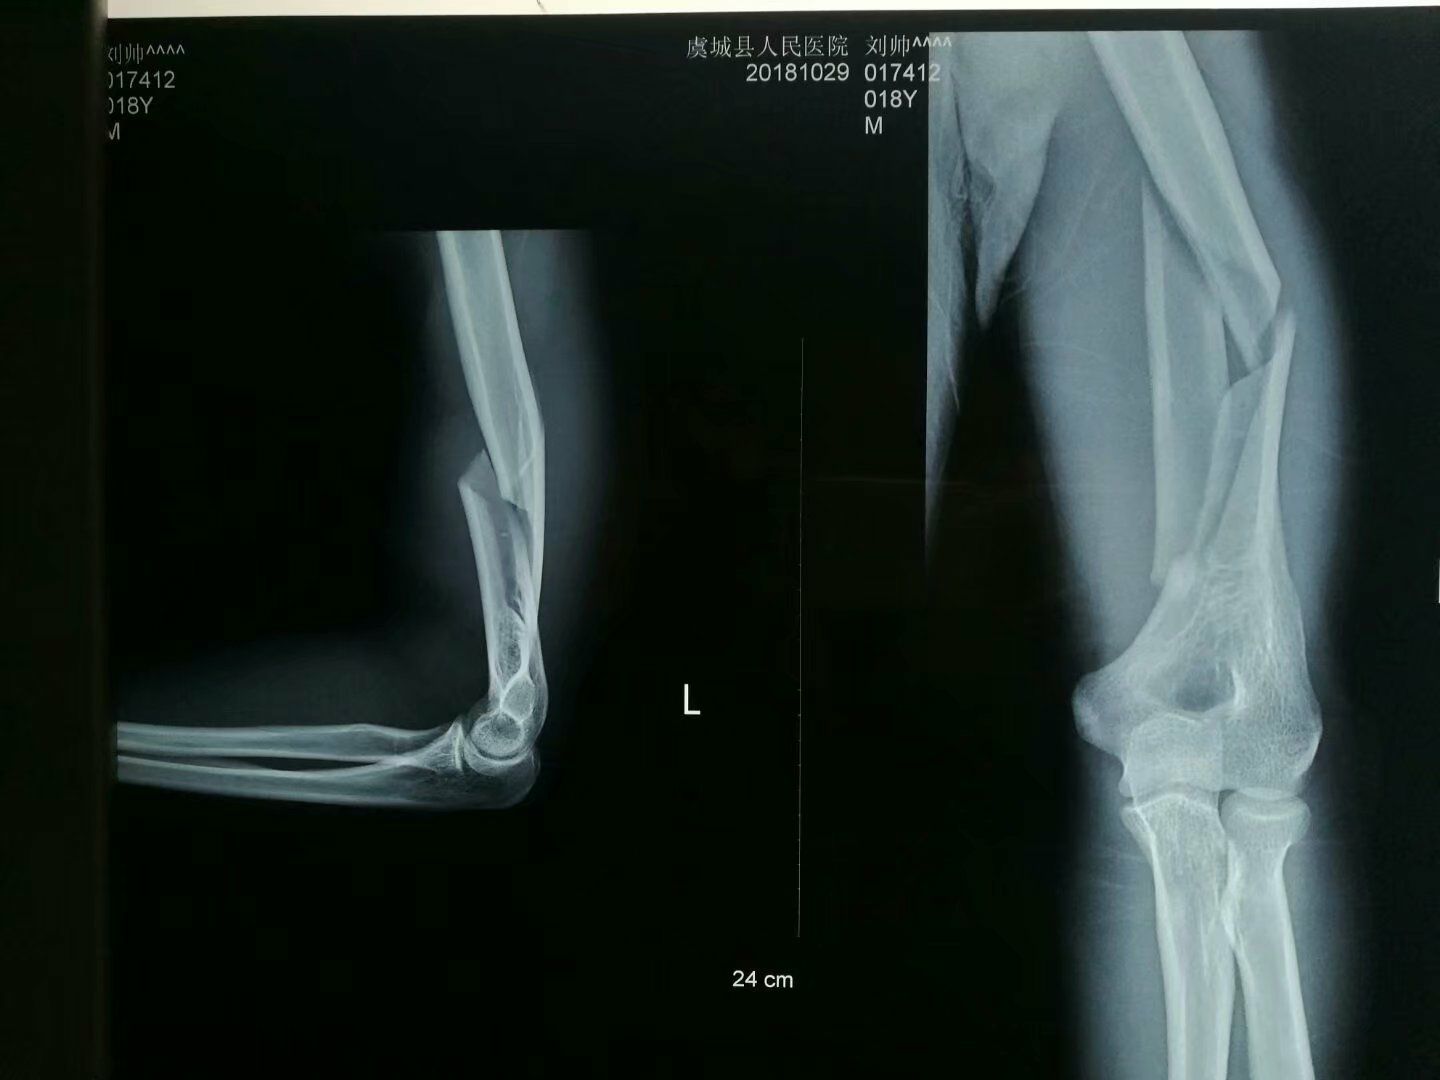

肱骨中下段骨折治疗

患者18岁男性,因掰手腕导致左肱骨中下段疼痛活动障碍入院,左手活动感觉良好。

X线片:左肱骨中下段粉碎性骨折。

入院诊断:左肱骨中下段粉碎性骨折。

左肱骨下段骨折,骨折线较长,髓内钉工作区域不合适,内外侧板?亚髁板?

正位满意

固定满意